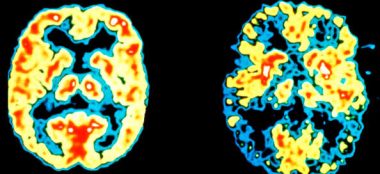

#Хвороба_Альцгеймера – це прогресуюча форма деменції. Деменція – це ширший термін для станів, що негативно впливають на пам’ять, мислення та поведінку. Ці зміни заважають повсякденному життю. Деменція може бути спричинена цілою низкою причин, наприклад травмами головного мозку або захворюваннями. Іноді Read More